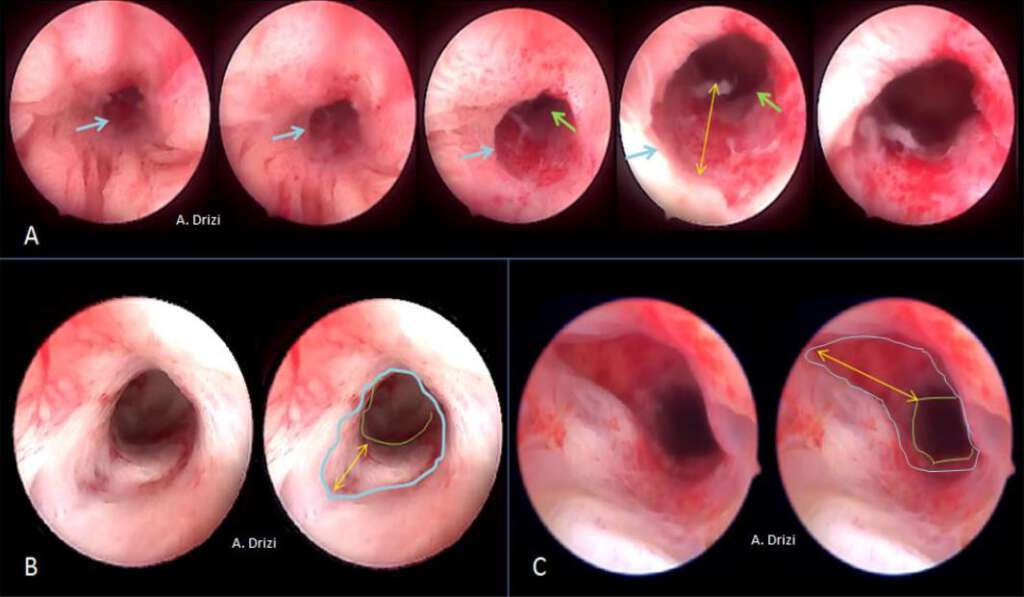

The main differential diagnosis of EH without atypia is the late secretory phase and the dysfunctional inflammatory endometrium (3, 5). Atypical EH, also termed EIN, and EC however are likely to display similar patterns both hysteroscopically and histopathological (28). EM received higher attention from authors and different classifications have been proposed by different researchers to improve the hysteroscopic identification of the suspicious lesions to be visually biopsied. The neoplastic processes are categorized by their morphological external appearance. The terminology proposed by these classifications describe tumors as nodular (bulging), polypoid (thin pedicles), papillary (numerous dendritic projections), glomerular (polypoid with papillary-like component containing atypical neo-vessels covered by a thin layer of endometrial tissue) and cerebroid (nodular or polypoid with abnormal surface vessels) (29) (fig 17). Other terms were proposed by other authors such as ulcerated (endophytic) patterns and cotton-candy like (presence of necrosis) (29).

However, regardless of the terminology used in these different classifications, all seem to agree on the same morphologic criteria suggestive of atypical EH/EM and which are vascular, glandular and epithelial. Consequently and educationally speaking, it could be more interesting to focus on the analytic details of the tissue and vessels instead of the various classifications themselves. Those criteria indicate the site where the biopsy has to be performed, as all researchers confirmed their suspiciousness and use them to assess the risk in the above mentioned classifications. In addition to the lesion’s thickness (10 mm or greater) and its extension to the cervix, the morphologic epithelial criteria to be particularly careful about are illustrated in fig 18 and consist of an irregular surface (polypoid, endophytic or exophytic projections), heterogeneous colors (whitish-grayish without vessels on the surface: indicators of glandular back-to-back overcrowding; yellowish or whitish cotton-candy aspect as indicator of necrosis). The more the tissue is friable and hemorrhagic at hysteroscopic manipulation, the more suspicious (fig 18). And just as importantly, the characteristic suspicious vascular patterns present with irregular diameter, irregular ramifications, brutal interruptions and serpiginous trajectory forming loops at places (29,30) (fig 19).

Figure 17. Frequently used terminology in classifications based on the morphological appearance of endometrial cancer. A: polypoid (thin pedicles). B: papillary (numerous dendritic projections); C: nodular (bulging); D: glomerular (polypoid with papillary-like component containing atypical neo-vessels covered by a thin layer of endometrial tissue); E: cerebroid (nodular or polypoid with abnormal surface vessels); F: cotton-candy like pattern (necrosis).

Figure 18. The morphological epithelial patterns suggestive of atypical EH/EM requiring attention and sampling. A: irregular surface (polypoid, endophytic or exophytic projections); B: heterogeneous colors: whitish-grayish surface without vessels (w) (back to back glands); yellowish (y) (necrosis); C: yellowish and whitish cotton-candy aspect (necrosis); D: friable hemorrhagic tissue both at hysteroscopic manipulation and at macroscopy.

Figure 19. The morphological vascular patterns suggestive of atypical EH/EM requiring attention and sampling.

A: irregular diameter; B: irregular ramifications and brutal interruptions; C: serpiginous trajectory forming loops at places; D: different atypical vascular patterns at microhysteroscopy. Images by A. Drizi